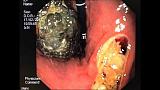

На ЭГДС фитобезоар около 10х6х5см + язва-пролежень с признаками состоявшегося кровотечения.

1. и 2. эндофото- амбулаторный приём, образование каменистой плотности, форцепт соскальзывает с поверхности при инструментальной пальпации, назначена "кока-кола Терапия".. + госпитализирована в хирургическое отделение..

4. и 5. Эндофото, образование размягчилось и режется/фрагментируется корзинкой-литотриптором..